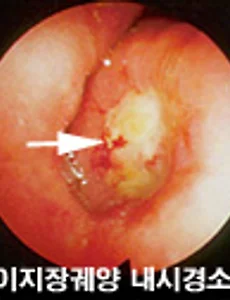

만성 십이지장 궤양 구부 변형 치료 및 예방 방법 어머니가 의료보험에 실시한 위암 검진을 받았는데, 만성 십이지장 궤양 구부 변형으로 의사와 상담을 요망한다고 해서 무슨 질환인가 하고 찾아봄... 십이지장에 발생하는 궤양. 호발부위(好發部位)는 위의 출구인 유문부(幽門部)에서 십이지장으로 이행하는 기발부(起發部)인 십이지장구부(球部)이다. 위궤양과 함께 소화성 궤양이라고 하며, 위궤양의 경우보다 젊어, 20대에서 흔히 볼 수 있고 특히 남자에게 많다. 궤양은 깔대기 모양이며, 그 선단은 외측, 즉 장막면(漿膜面)을 향하여 깊이 침식한다. 원인은 위궤양과 마찬가지로 여러 가지 인자가 고려되고 있다. 증세는 동통이며, 이것은 상복부의 정중선(正中線) 오른쪽에 여러 정도의 통증을 느끼며, 오른쪽 견갑부(肩甲部)나 오른쪽 하지로 자주 방산한다. 공복통이 많다... 2010. 4. 5.